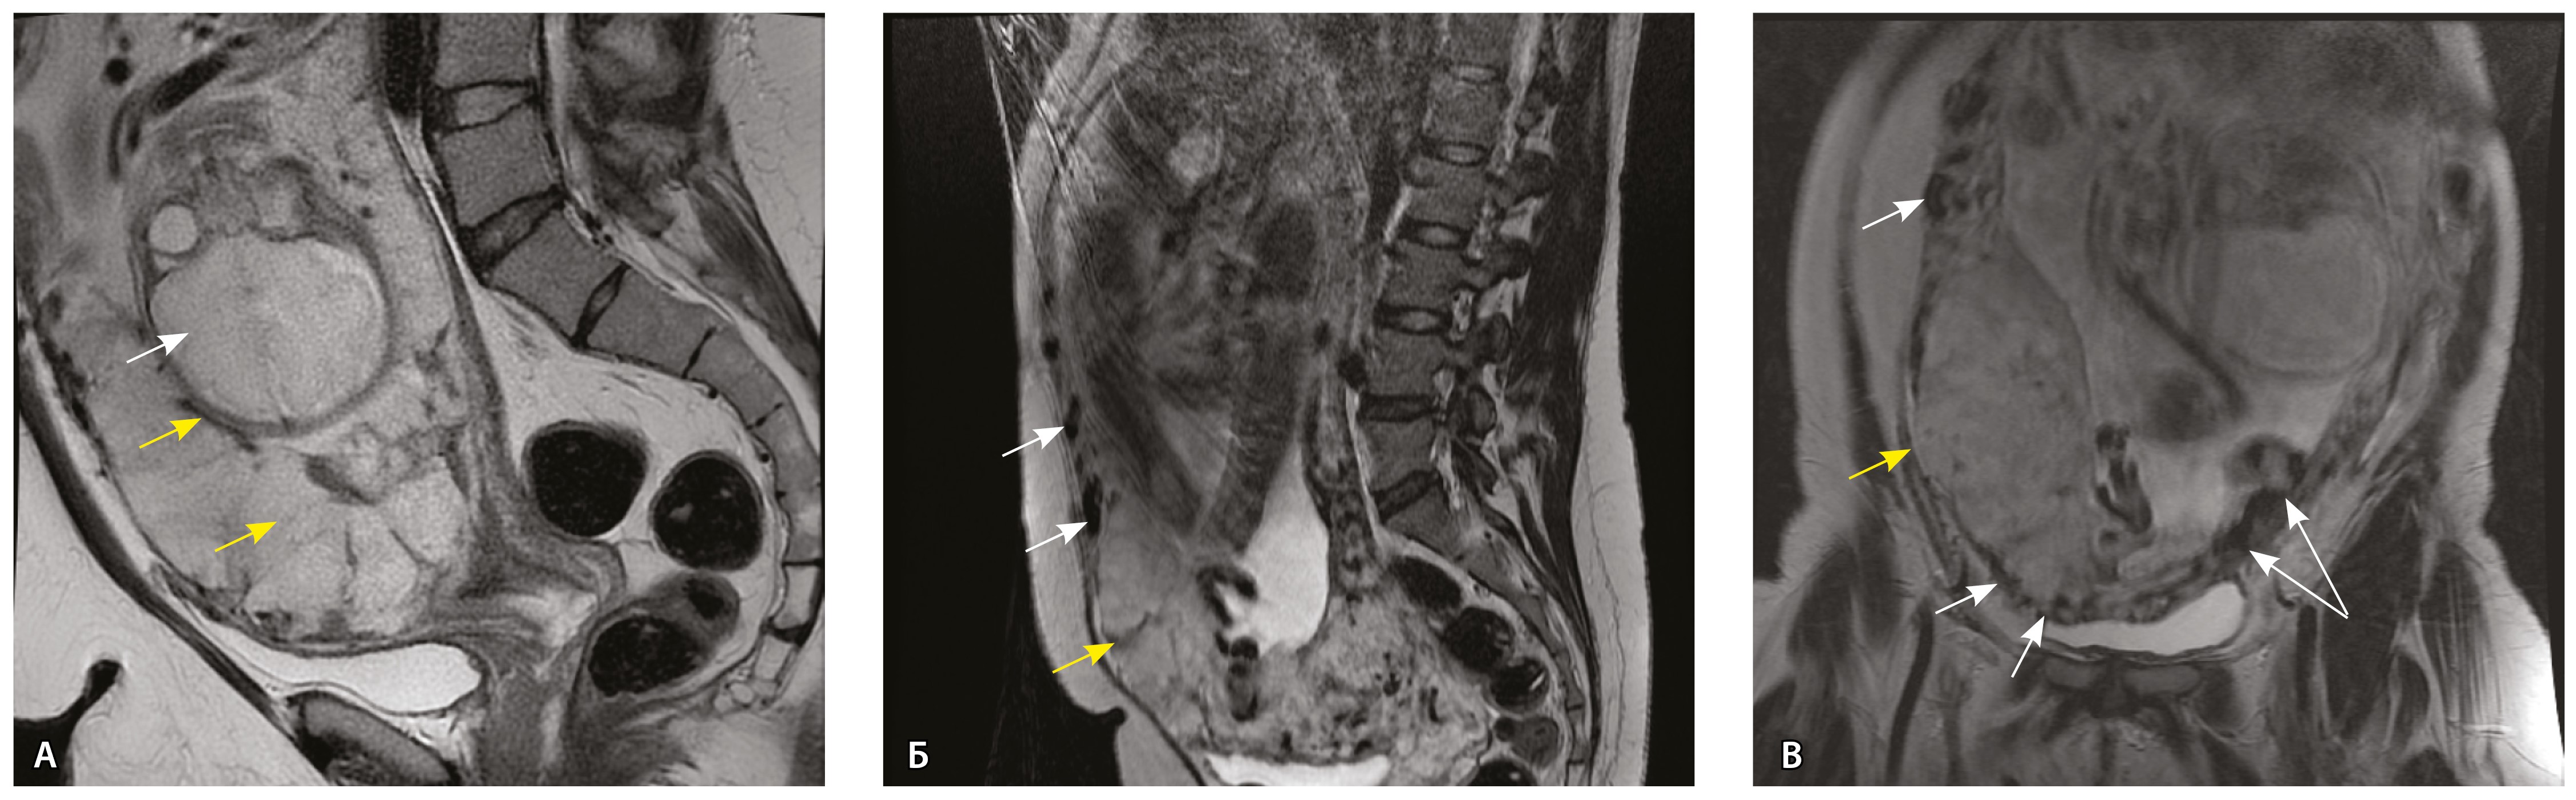

Рис. 10. Беременность 33 недели, pl. percreta, PAS 3a по FIGO. На магнитно-резонансных томограммах в режиме Т2-взвешенного изображения в сагиттальной (A) и фронтальной (Б, В) плоскостях определяется внутриматочная гиперваскуляризация (желтые стрелки) и гиперваскуляризация в области выраженно истонченного нижнего маточного сегмента, с наличием многочисленных анастомозирующих сосудов по поверхности матки (белые стрелки); стенка матки в данной области представлена ретроплацентарными сосудами

Сосуды 5-го типа. Наличие гиперваскуляризации за пределами матки по данным МРТ, на границе с мочевым пузырем с вовлечением его стенки, сосуды в области перешейка матки, параметрия, в том числе в сочетании с признаками фиброза, наличием рубцово-спаечных изменений и др. Можно предположить, что сосуды 5-го типа являются аналогом pl. рercreta PAS 3b, 3c (рис. 15).

Рис. 15. Беременность 34 недели, pl. percreta, PAS 3b по FIGO (A, Б), PAS 3c по FIGO (В). На магнитно-резонансных томограммах в режиме Т2-взвешенного изображения в сагиттальной (A, В) и аксиальной (Б) плоскостях определяется гиперваскуляризация в области выраженно истонченного нижнего маточного сегмента с распространением сосудов на заднюю стенку мочевого пузыря в области дна (белые стрелки), в область перешейка матки (желтые стрелки)